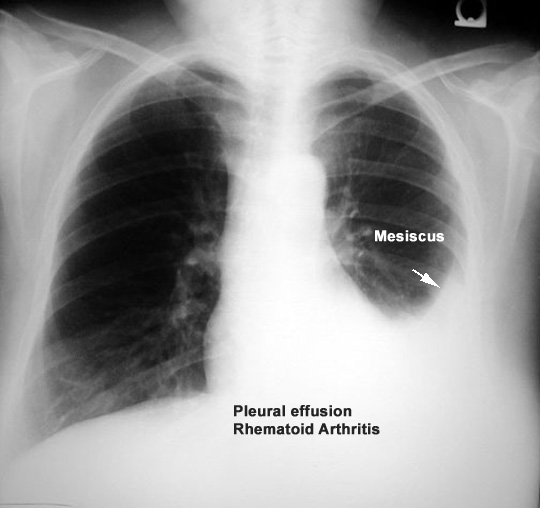

Findings:

- Density

- In dependent portion

- Costophrenic angle in PA view

- Silhouette of upper limit of density

- Upper margin high in axilla in PA view

- Blunting of costophrenic angle

- Lack of identifiable diaphragm (silhouette sign principle

Diagnosis

Rheumatoid Pleural Effusion